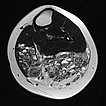

In der axialen T2-gewichteten MRT des linken Unterschenkels finden sich mehrere dilatierte, dysplastische Venen im Sinne einer venösen Malformation in der gesamten oberflächlichen Flexorenmuskulatur. Durch den niedrigen Durchfluss kommt es zur Stase des Blutes innerhalb der Malformation mit der Bildung von Flüssigkeits-Spiegeln. Praktisch der gesamte Muskel ist von Malformation und Fettgewebe durchsetzt. Großer Thrombus in einer dilatierten, dysplastischen Vene.